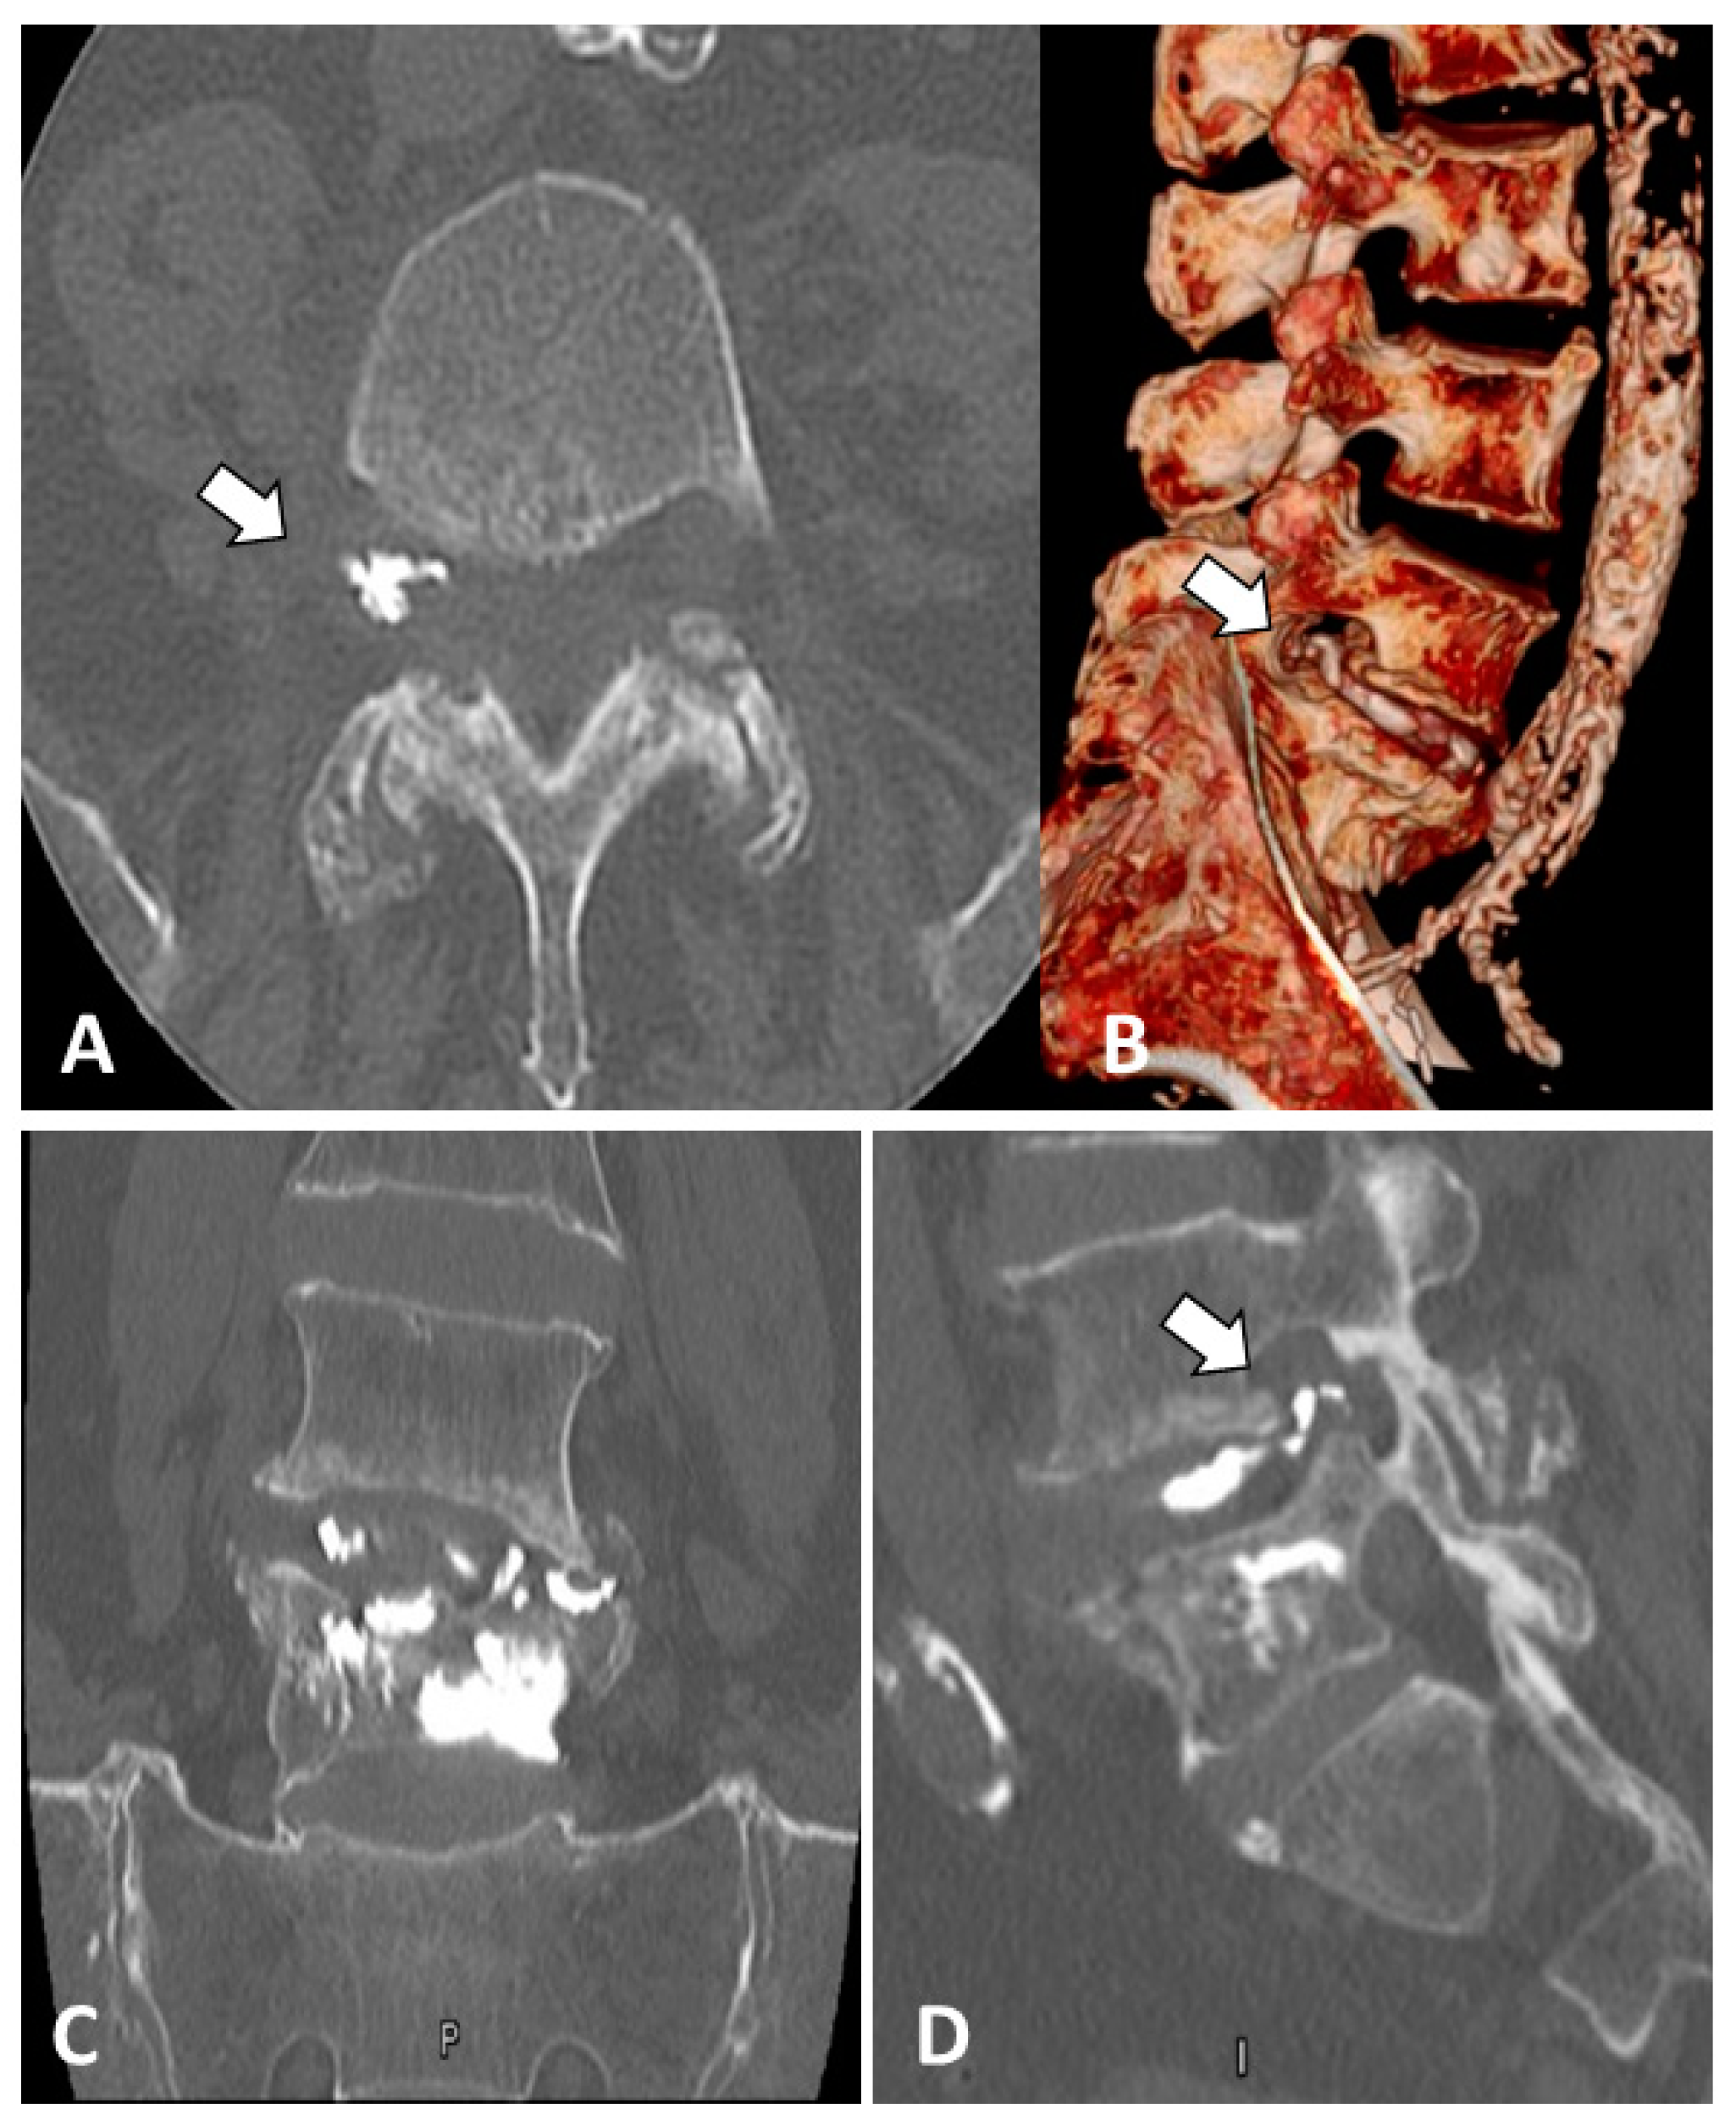

2. Case Report